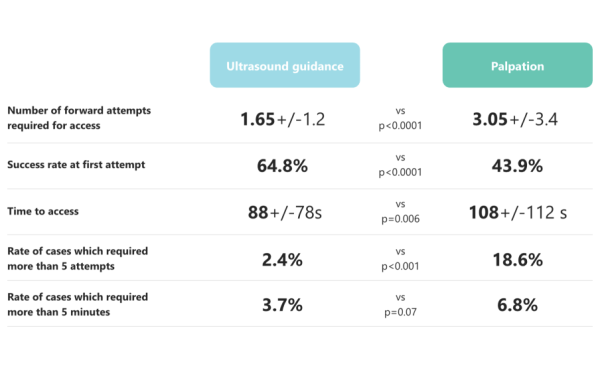

- Sure! The graph below sheds light on the relationship between the two. You can determine vessel size using ultrasound, which, according to some data, can also improve puncture success rate.

If ultrasound is not an option, using contrast and fluoroscopy is a viable alternative.